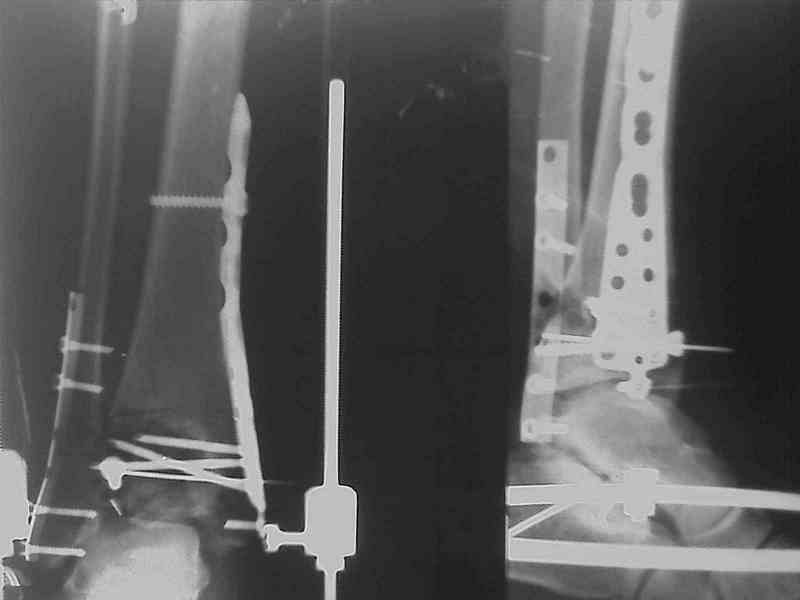

Снова приветствую вас, коллеги. К моменту вступления в обсуждение аксакалов, операция была, увы, выполнена(31.10.07.) Начали с доступа к наружной лодыжке, произвели ее фиксацию спицами, развернули кусок заднего края, наложили дистрактор, затем произвели дистракцию, фиксацию спицами дистального эпиметафиза б/бк,Рентгено-контроль. синтез наружной лодыжки 1/3пластиной. из двух коротких разрезов сформирован канал под медиальную тибиальную пластину LCP. Края ран ушиты без натяжения. Прочувствовать жесткость фиксации винтами с угловой стабильностью не удалось, поэтому дистрактор оставлен на энное время.

На представленных R-снимках не окончательный вид после остеосинтеза. Дистальная опора давила на стопу, пришлось ее сместить проксимально, в рез-те чего, она закрыла щель сустава, последние снимки не информативны.

Дистальные винты как-то чуть не все идут не в дистальные отломки, а в зону перелома. И действительно, присоединяюсь к вопросу Якова - в диафизе так и оставили 1 винт?

Мне тоже кажется, что имея в дистальном отломке один блокированный винт (в медиальной лодыжке), а остальные в зоне дефекта, где должна была бы быть костная пластика, стабильности ждать не приходится.